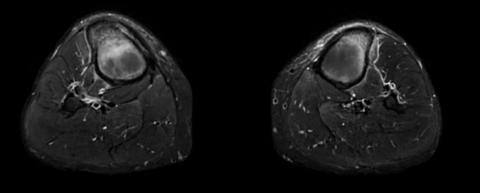

Séquence axiale.png

Séquence axiale 2.png

Séquence axiale DP FS montrant un oedème médullaire

osseux avec épaississement cortical.